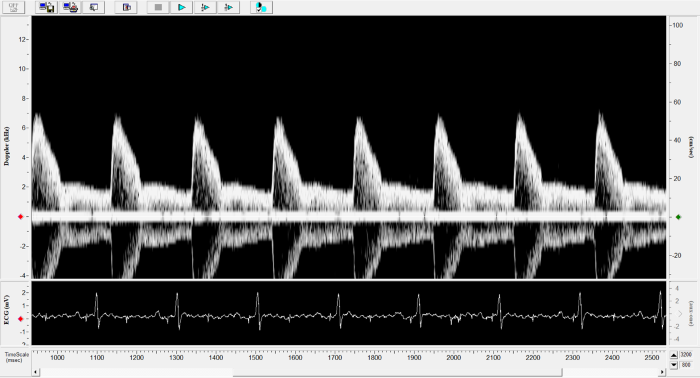

Imaging gallery - Doppler Flow Velocity System

Carotid Image. Image Credit: Scintica Instrumentation Inc.